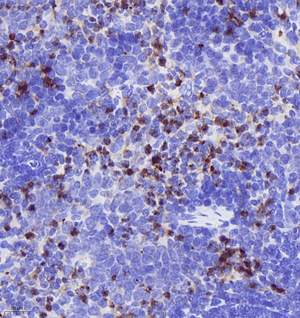

| IHC analysis of MPO (GB11224). Sample: Rat spleen (Paraffin), 4% PFA (G1101) 12-24h. Antigen retrieval: Citrate buffer (pH 6.0) (G1201),98°C,20 min. Blocking buffer: 3% BSA in PBS (GC305010), RT, 30min. Primary antibody: 1: 3000, 4°C overnight. Secondary antibody: HRP Goat Anti-Rabbit lgG (GB23303), 1: 200 RT 1h. |